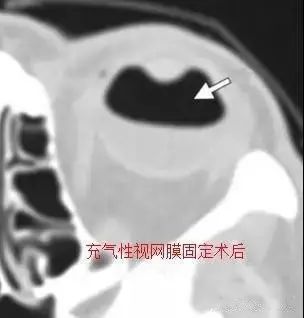

3.常见的用于治疗视网膜脱离的材料包括巩膜条带 , 硅油 , 以及气体 。

文章插图